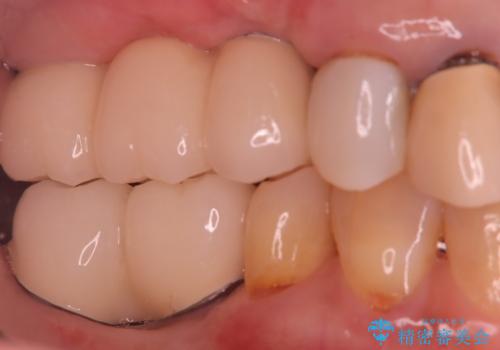

インプラント埋入手術は1回で全て行い、2ヶ月後にはセラミック治療で、審美回復と機能回復をしました。

来院回数が少なく、しっかり食事もできるとの事で非常に喜んで頂けました。